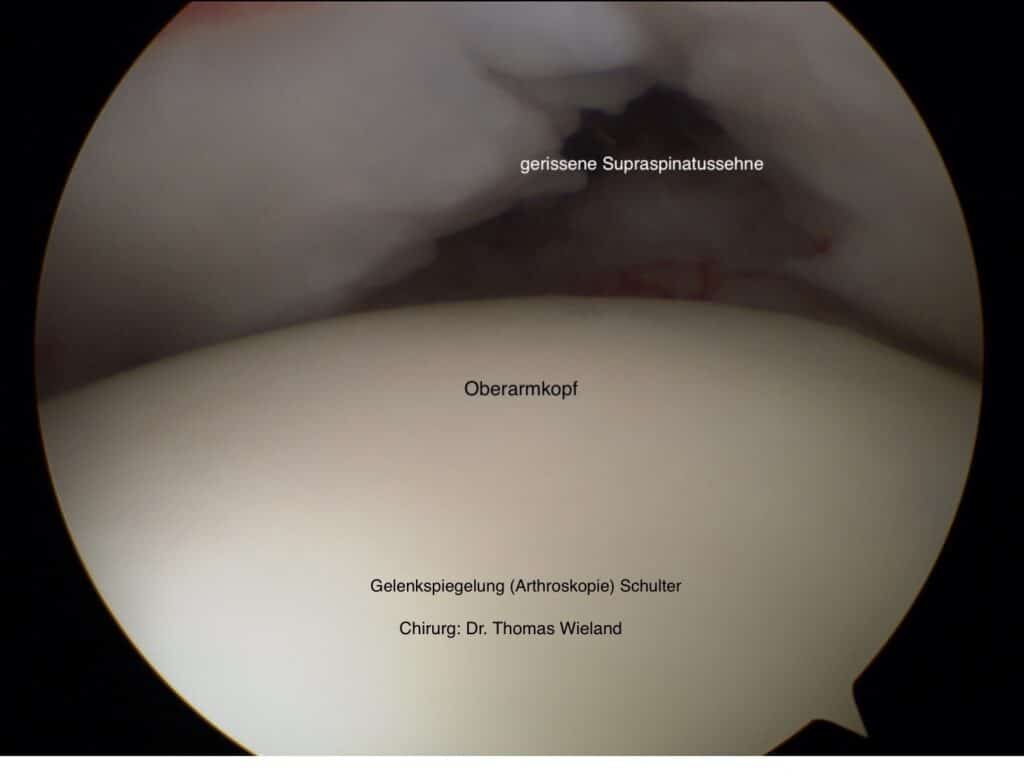

Bereits kleinste Überlastungsschäden, auch Mikrotraumen genannt, können zu Schäden und spontanen (Ein-)Rissen in diesem empfindlichen Bereich Ihrer Schulter führen. Daraus können erhebliche Schmerzen an der Schulter für Sie resultieren.

Wenn Sie von Schmerzen in der Schulter betroffen sind, ist es ratsam, den Arzt Ihres Vertrauens aufzusuchen, denn unbehandelt können solche kleinen Verletzungen zu größeren Spätschäden führen.

Ihr Arzt stellt mithilfe einer gezielten Befragung und Untersuchung schnell fest, ob es sich um ein Verletzungsmuster an der Schulter im Bereich Ihrer Rotatorenmanschette handelt. Durch weiterführende Untersuchungen, wie eine Magnetresonanztomographie (MRT) und Röntgen an der Schulter, lässt sich der erste Verdacht untermauern und der Schwergrad der Verletzung an der Schulter zielgerichtet erheben.